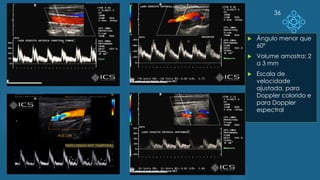

36

 Ângulo menor que

60º

 Volume amostra: 2

a 3 mm

 Escala de

velocidade

ajustada, para

Doppler colorido e

para Doppler

espectral

Doppler de Carótidas Registro mínimo